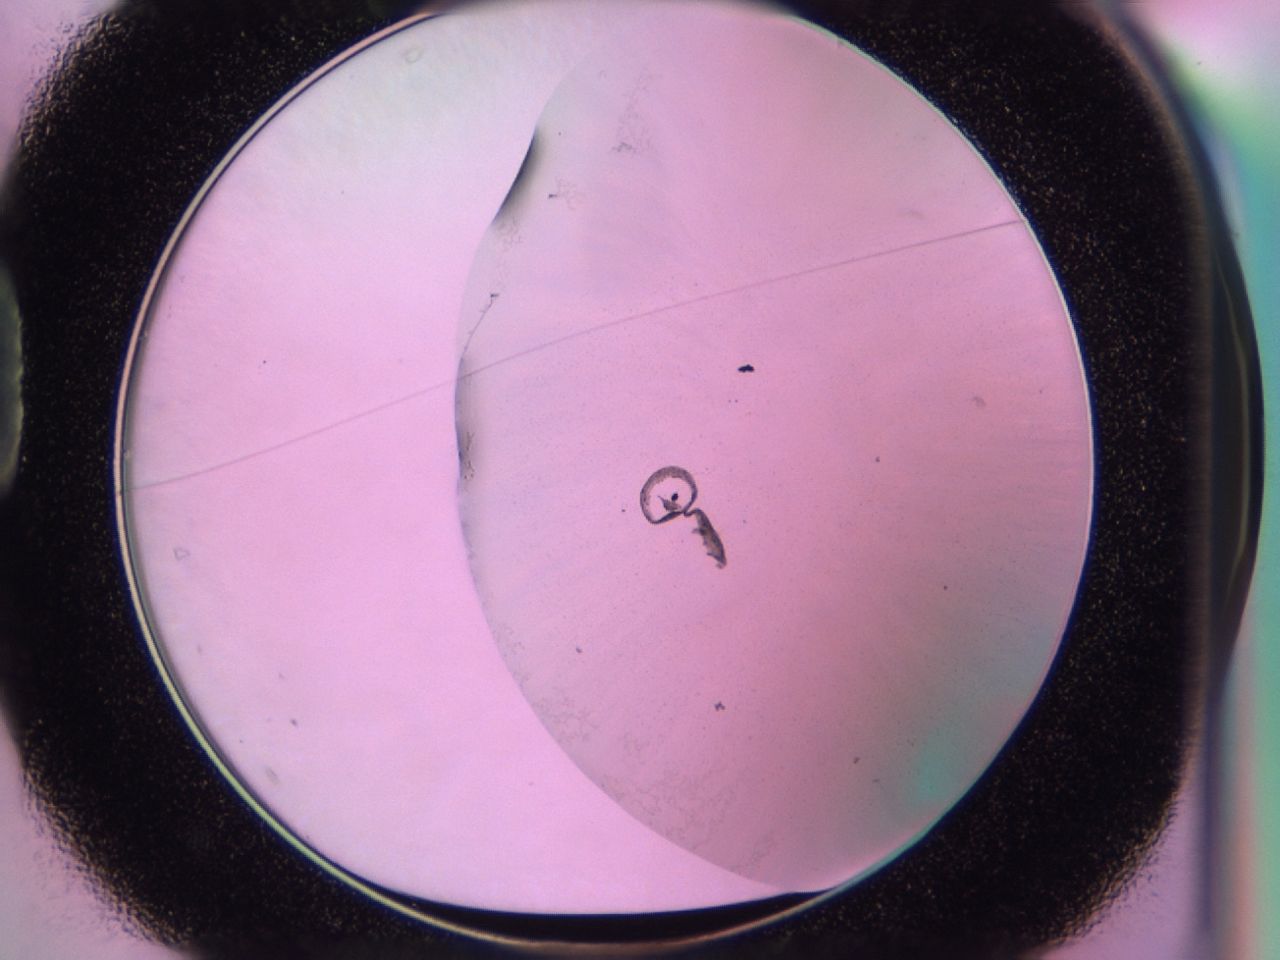

Image 3236

018k_D1_ImagerDefaults_1.jpg